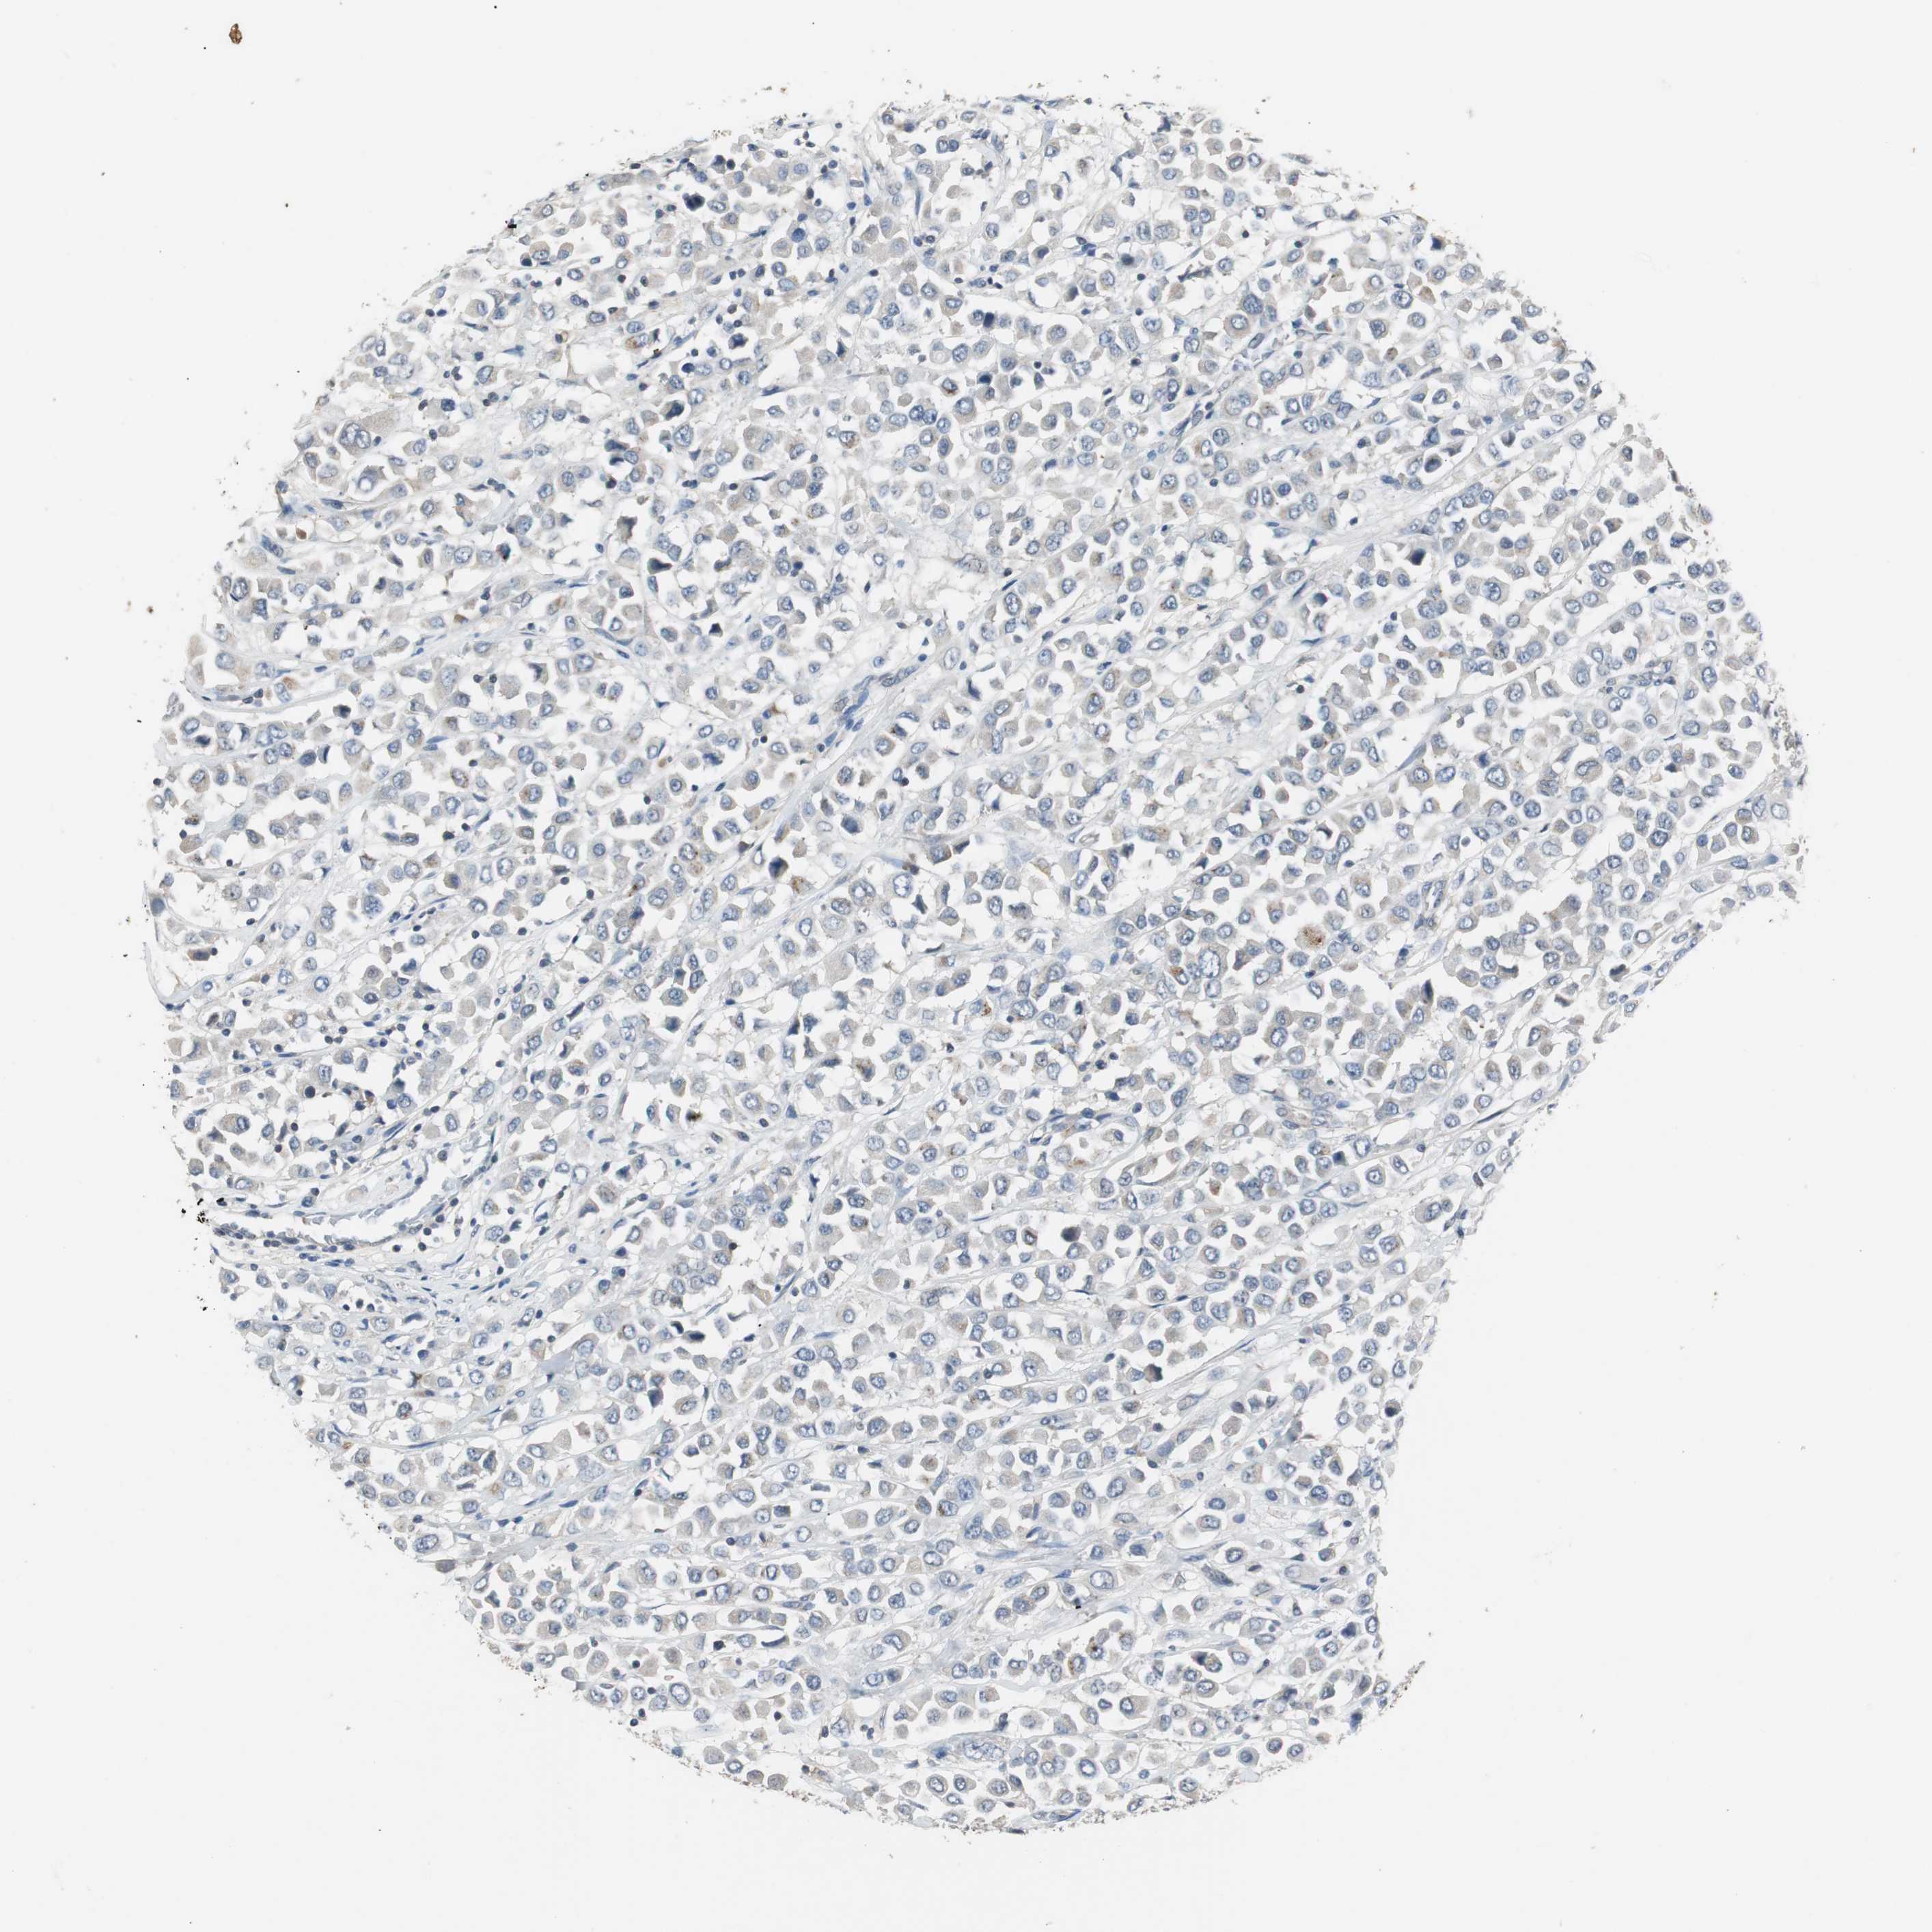

CANCER BREAST CANCER Show tissue menu

BRCA TCGA BRCA VALIDATION PROTEIN EXPRESSION